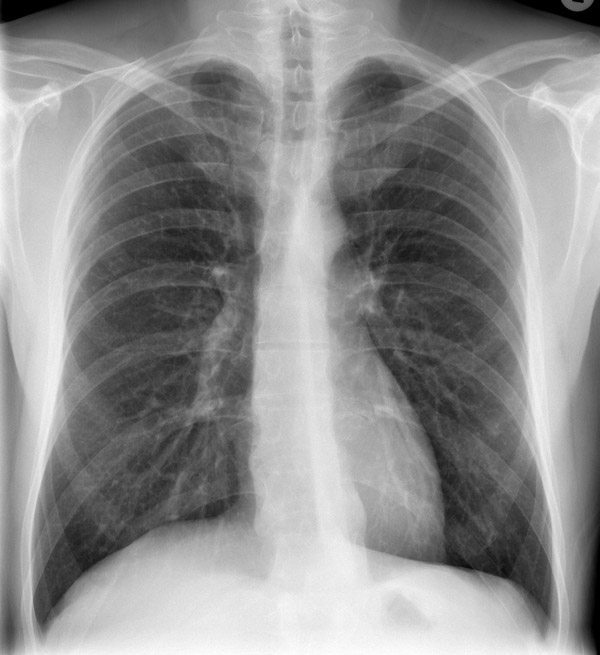

-

рентгеновский снимок: локализация в верхнем сегменте левой нижней доли

На рентгене определяются изменения бронхов и легочного интерстиция, а также очаговая, сегментарная или долевая инфильтрация, воспалительные уплотнения, усиление легочного рисунка. Чаще эти изменения обнаруживают с одной стороны в нижних легочных полях.